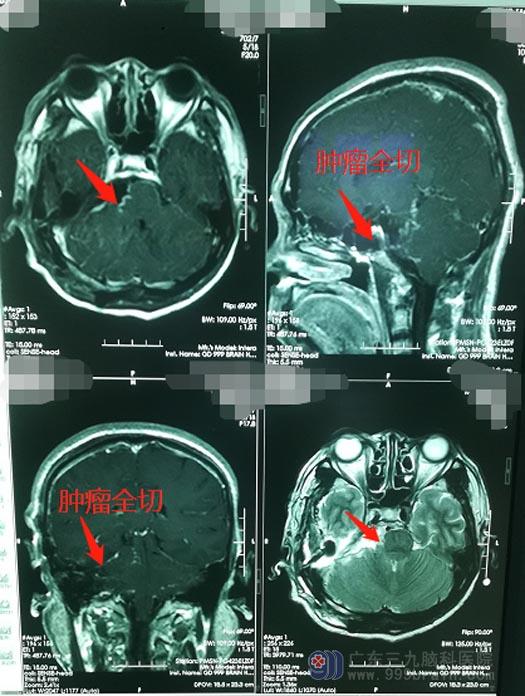

为确保手术成功,神经外五科团队仔细分析了邓大哥的病情,判断全切的可能性,精心设计了完备的治疗方案及手术入路,由鲁明带领手术团队实施“右侧颞下联合乙状窦后入路行岩斜区跨中后颅窝脑膜瘤切除术”。术中,在显微镜下对肿瘤进行精细剥离,各组颅神经保护良好,成功将肿瘤全部切除。术后,邓大哥神志清醒,没有出现颅神经损伤的表现,意识清楚,说话流利,肢体活动正常。

▲手术后